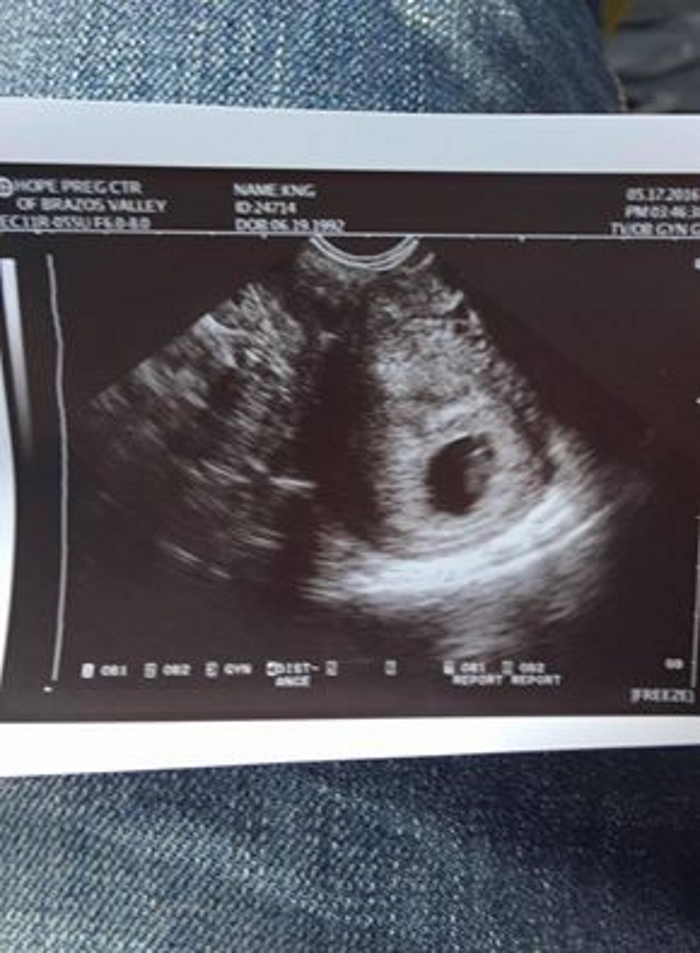

Inicialmente, los médicos informaron que todavía lograban escuchar los latidos del corazón del feto en el útero. Pero, unas horas más tarde, tuvieron que admitir que el niño también murió. Solo restaba extraer su cuerpecito sin vida del vientre de su desdichada madre.

«En esta foto, yo estaba acostada, unas pocas horas después de haber perdido a mi marido y a mi hijo no nacido. Esto ocurrió porque alguien decidió beber y ponerse al volante – ¡Qué gran idea!»– dice Cristiana.